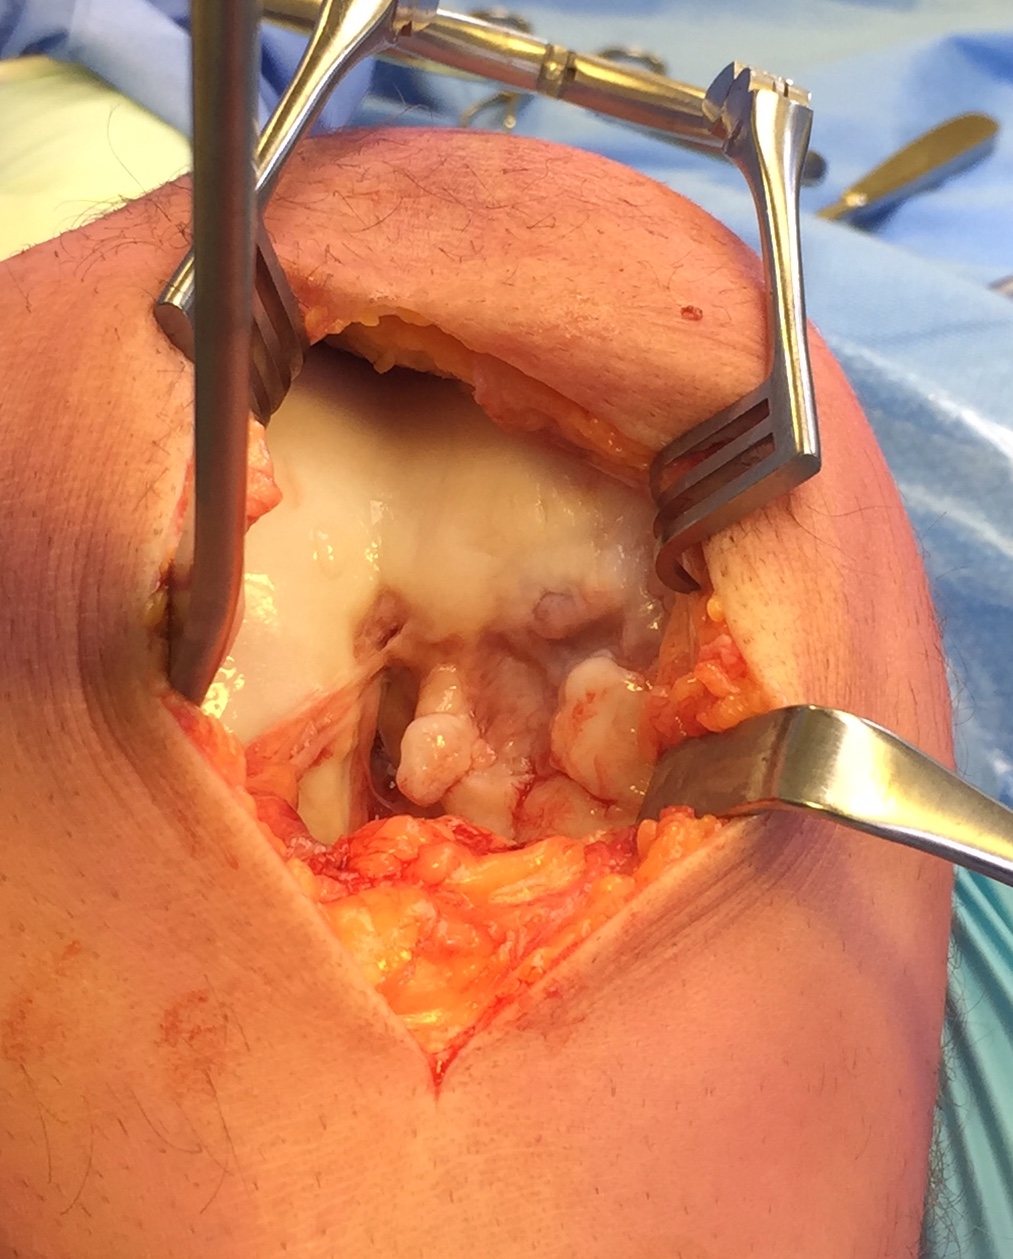

LFC unstable OCD